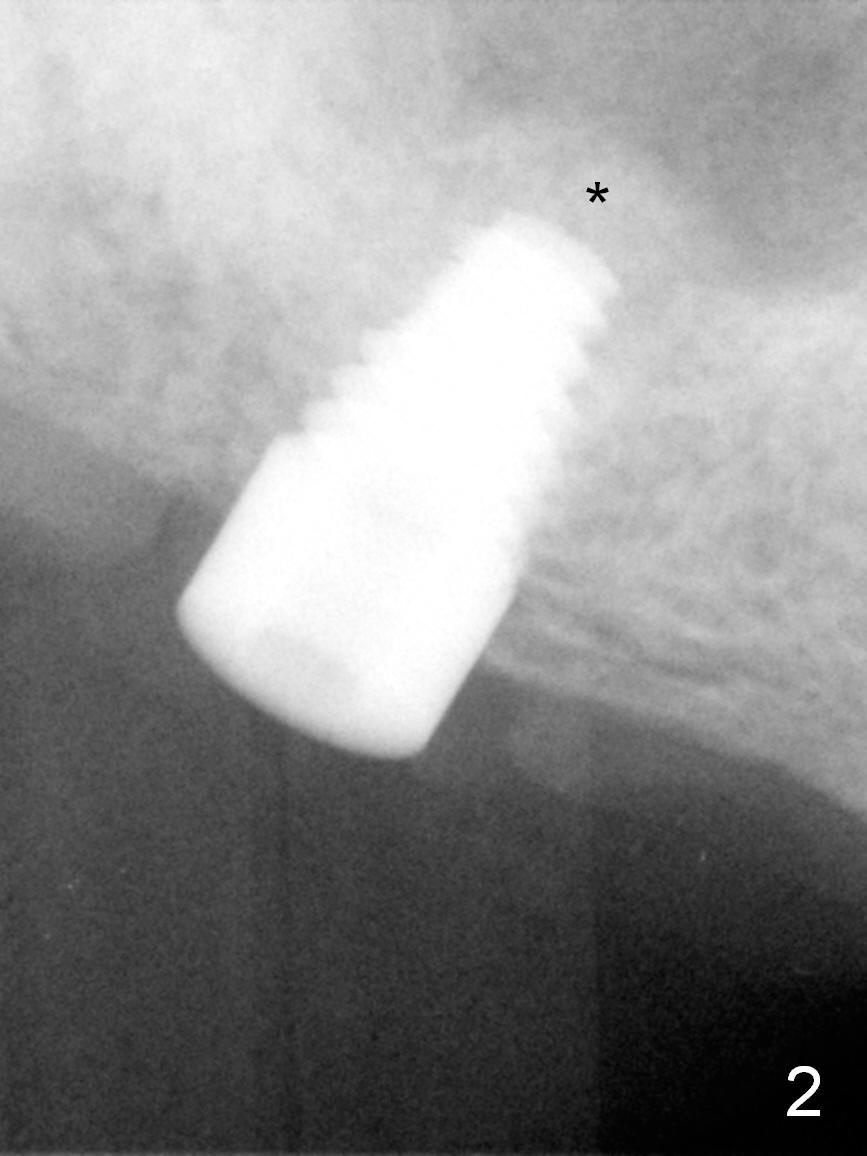

As planned, the osteotomy at #3 is underprep (using 3 mm reamer), followed by taps until 5x11 mm (Fig.1). When a 6x11 mm implant is being placed with high torque (Fig.2 (*: sinus lift)), bone mesiobuccal to the implant is starting to green-stick fracture. After flap suturing, a 5x3 mm abutment is placed and adjusted for the height. In fact the long vertical edentulous space is an artifact. An immediate provisional is fabricated with clearance (Fig.3,4). The adaptation of the provisional to the implant/abutment is so good that cement is not necessary for retention. When the wound heals, the provisional is too short to be retentive. It is not recemented. A healing screw is placed until the implant is restored.